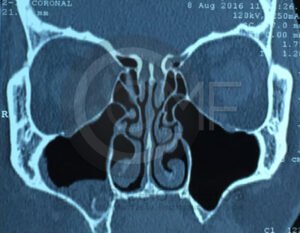

Es una conexión entre la cavidad oral y el seno maxilar que puede ocurrir tras extracciones o infecciones. Su tratamiento busca cerrar adecuadamente la comunicación para evitar molestias e infecciones sinusales.